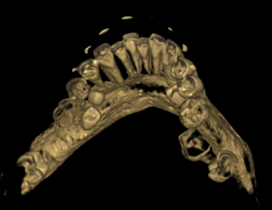

图2 CBCT可清晰显示左侧下颌骨的两个埋伏多生牙

图3 CBCT可清晰显示右侧下颌骨的两个埋伏多生牙